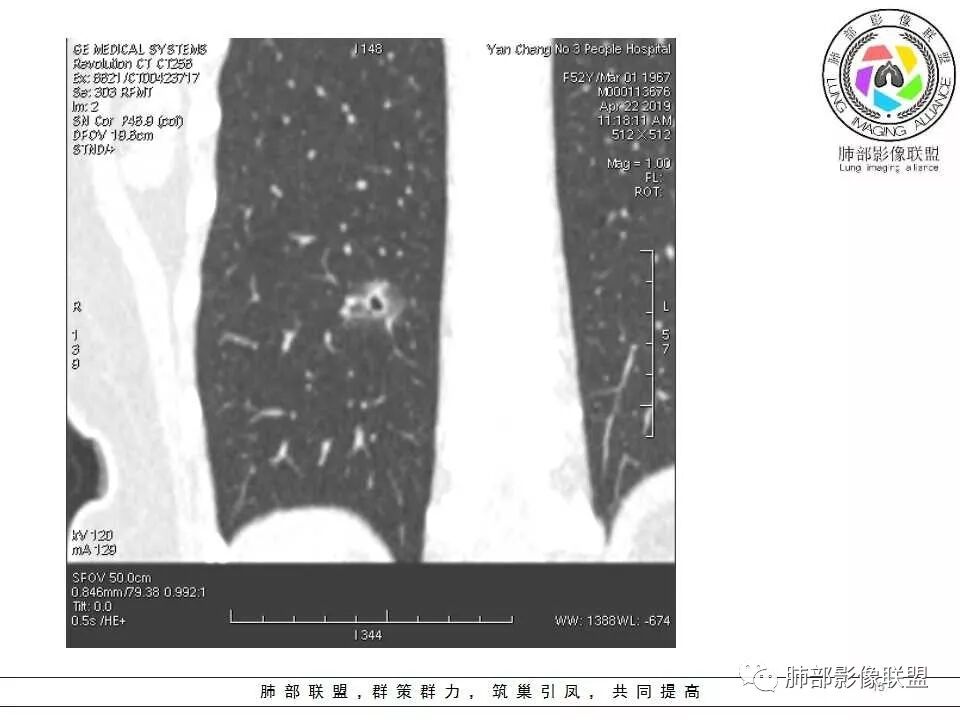

横断位看上去晕很模糊,冠矢状位重建后却比较清晰,所以单次CT检查蛮难定的,中心透亮区一定是空洞吗?我怎么觉得是一支气管壁有增厚,管腔有轻度扩张的支气管,第一感觉还是炎性结节吧,PC可能大,一定要否定腺癌也不敢,一个月左右复查。

体检发现肺部结节,右下肺混合密度结节,结节中心空泡,壁光滑,结节边缘模糊,血管在结节内增粗,矢状位前基底段还有一片磨玻璃影,所以考虑良性结节可能,炎性肉芽肿?抗炎后复查。腺癌合并炎性改变待排。

连续层面显示这个应该是空泡,或者小空洞,远端没有,近端也没有,周围环形软组织增厚。而空泡,影像上只是根据5mm界线,病理上不一定。

问一个问题,肺动脉肺静脉?为啥?

静脉,夹角90,周边没气管伴行。

静脉吧,动脉同时会伴有一根气管

这些呢?为啥?

动脉,有支气管伴行

伴有支气管

假如这是含气支气管,伴随的哪条动脉呢?近端从哪来?为啥环形壁增厚而又不均匀?都不太符合,所以支持空泡或小空洞。

上次刘纯老师提出,空泡征是一个影像征象,不是一个病理征象,我比较支持,他就是一个影像上的小低密度腔,原因很多,但是影像上与小的空洞表现区分不了。其中的原理:有一条是内容物排出后的残腔,其实也是空洞的原理。

大家考虑恶性的依据?炎性的依据?首先这是不是磨玻璃结节?依据是啥?

因为密度比肺组织高,但是又遮盖不了血管,所以GGO明确

是pGGO?mGGO?

实性的部分超过10%——mGGO

GGO边缘清不清?依据?

部分清,部分不清

依据:能不能沿GGO边缘画出一个边界

能否勾勒出边界?是否有血管?

排除血管的边缘,边界清吗?

可惜的是背景也模糊了一些